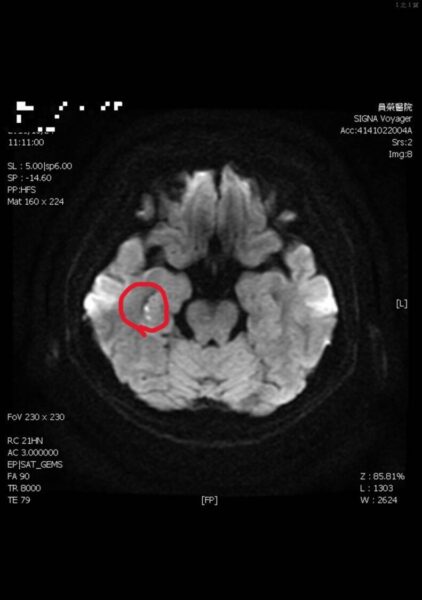

陳彥秀醫師表示,患者接受腦波檢查是正常;但核磁共振,看到她右側海馬迴出現一點亮亮的影像。海馬迴與記憶功能密切相關,證實她「短暫性全面失憶」狀況,是因為情緒過於激動,中風所造成。